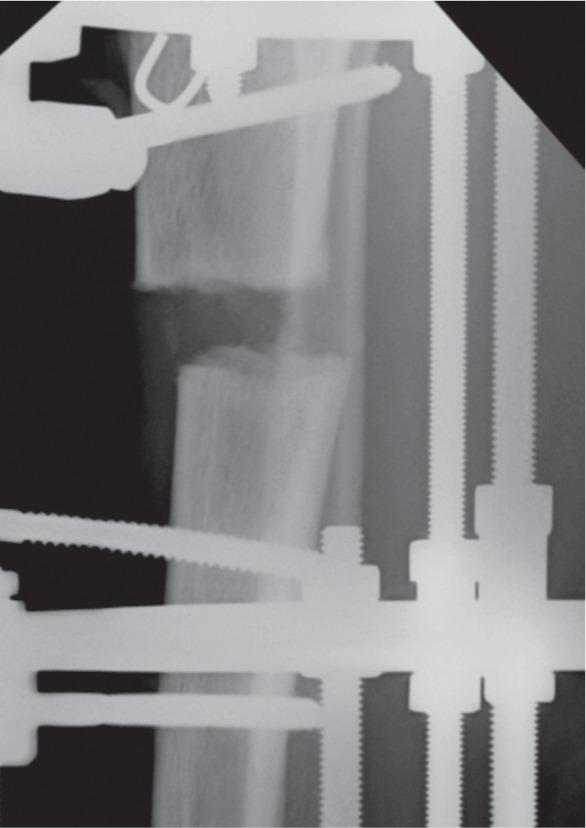

Corticotomy is an essential procedure for deformity correction and there are many techniques described. However there is no proper classification of the fracture pattern resulting from corticotomies to enable any studies to be conducted. We performed a retrospective study of corticotomy fracture patterns in 44 patients (34 tibias and 10 femurs) performed for various indications. We identified four distinct fracture patterns, Type I through IV classification based on the fracture propagation following percutaneous corticotomy. Type I transverse fracture, Type II transverse fracture with a winglet, Type III presence of butterfly fragment and Type IV fracture propagation to a fixation point. No significant correlation was noted between the fracture pattern and the underlying pathology or region of corticotomy.